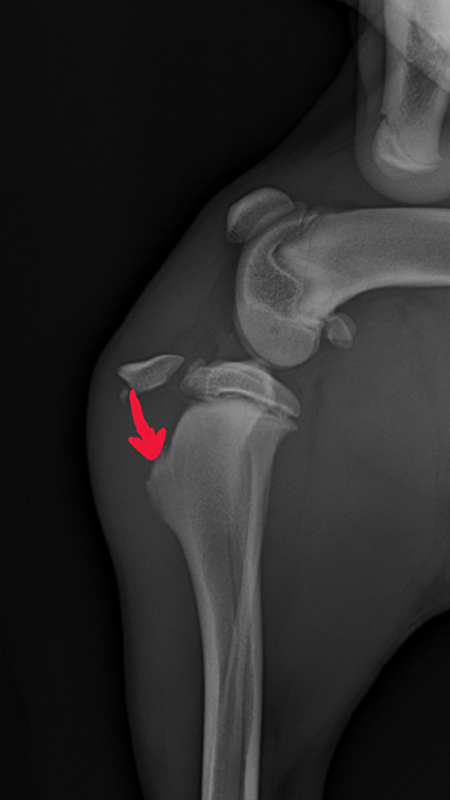

En toen pas ontdekten we de ellende

Z'n knie was Door de klap gebroken, je ziet op de foto heel duidelijk het los zittende stuk bot, en met de pijl de plaats aangegeven waar het bot normaal gesproken hoort te zitten: